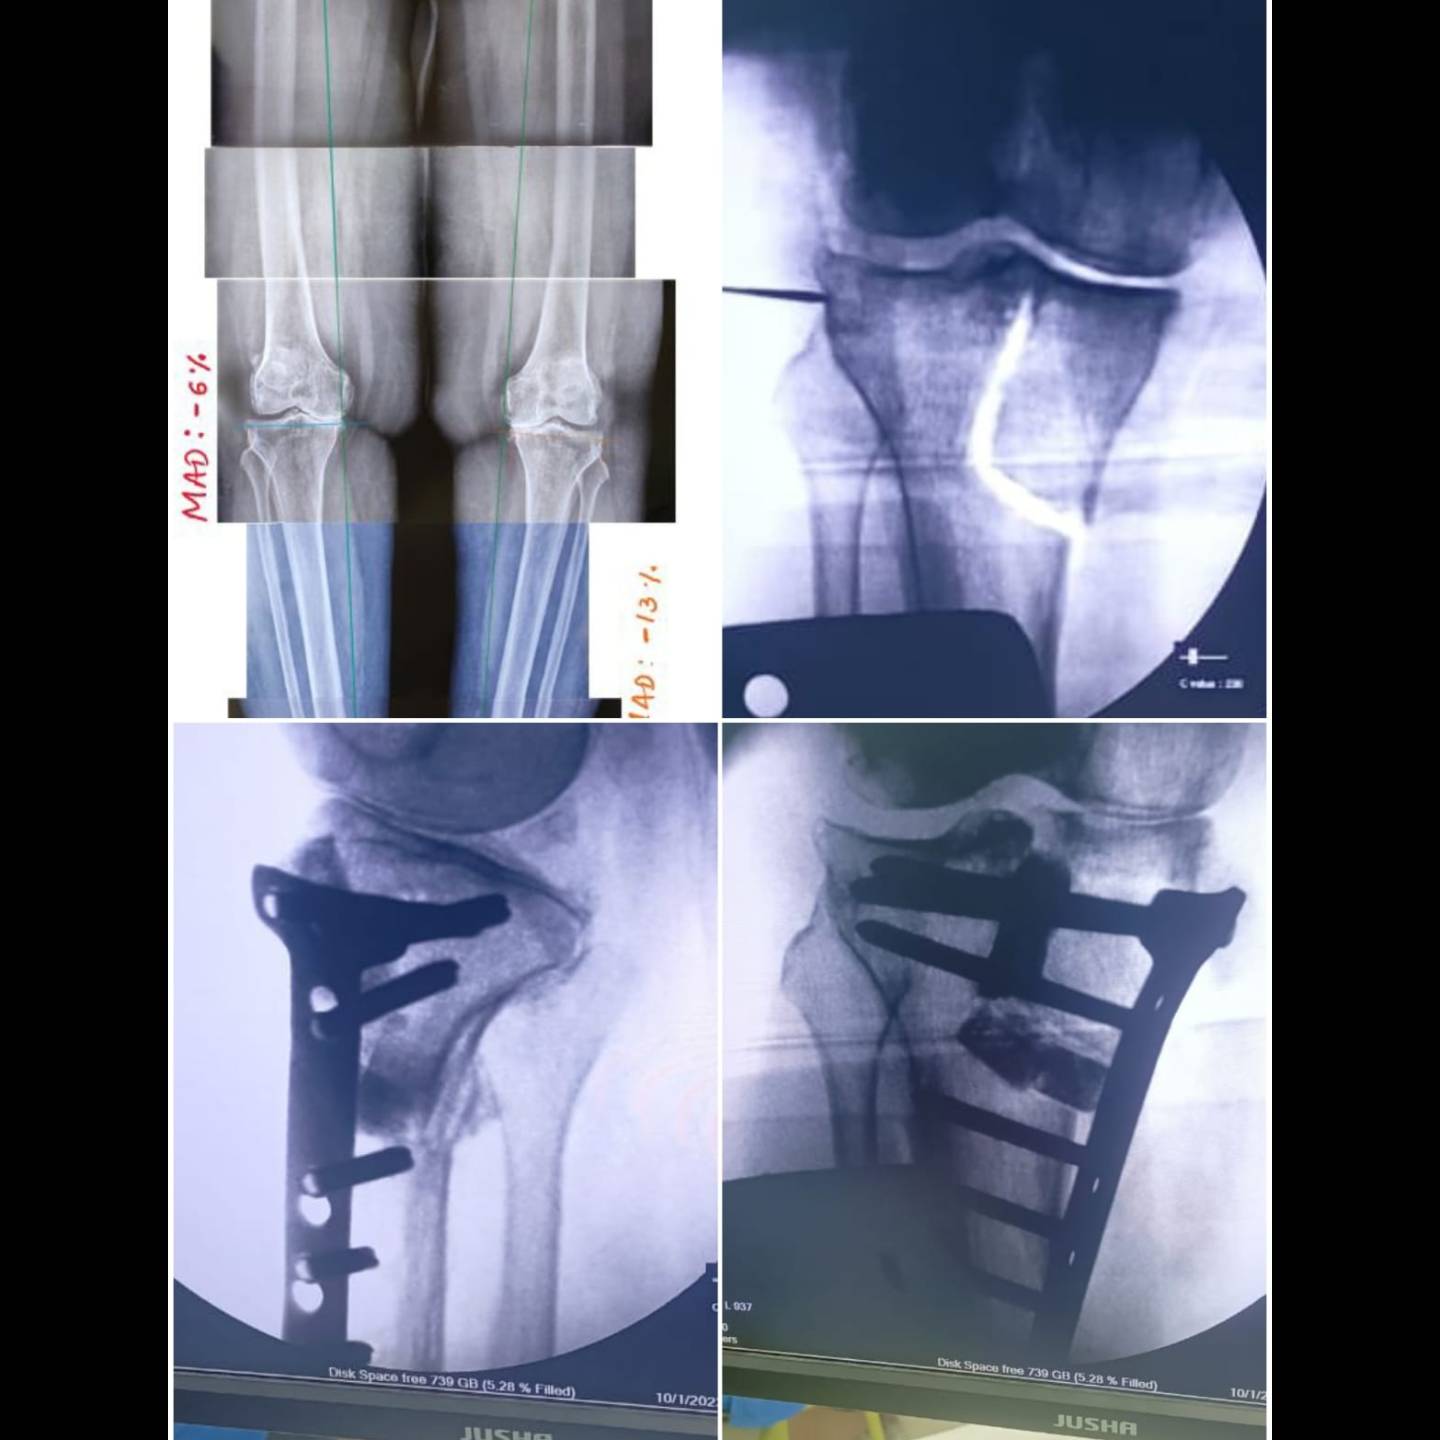

15 y old young girl with severe bow leg deformity.. ilizarov deformity correction.

45y young female with severe bow leg deformity... ilizarov deformity correction.

young female with knock knees..distal femur deformity correction.

Young female ...with knock knees..before and after complete correction of her deformity.